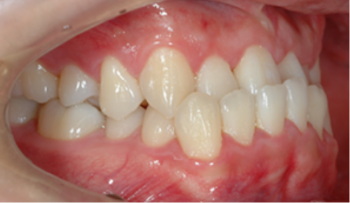

​​​​​​​Case 01. 덧니 & 치열 불규칙

덧니가 있거나 치열이 불규칙한 경우, 심미적으로도 보기에 좋지 않지만, 기능적으로도 본연의 역할을 상실하게 됩니다.

이 경우 교정 치료 방법은 크게 치아를 빼고 하는 방법과 치아를 빼지 않고 교정하는 방법으로 나뉩니다.

교정 치료 Before & After

• 덧니 & 치열 불규칙 교정 치료 전

Before

• 덧니 & 치열 불규칙 교정 치료 후

After